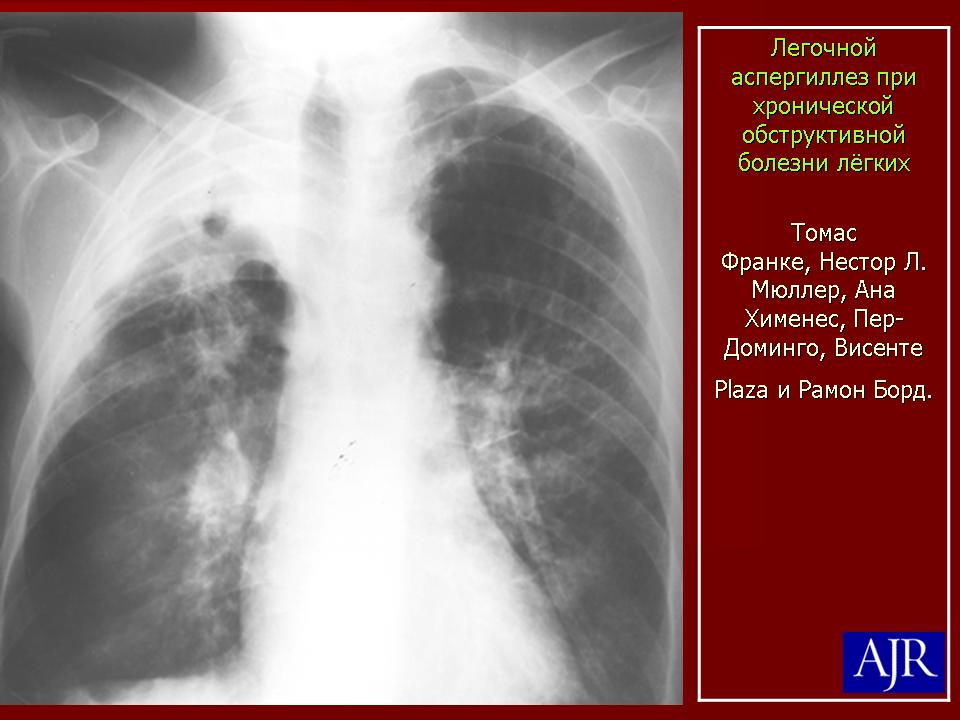

Визуализация и диагностика неинвазивного аспергиллеза с помощью КТ

Раздел: Необычные решения